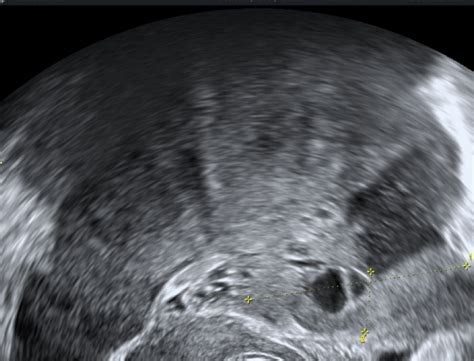

Med postopkom IVF se ženskam za spodbujanje jajčnikov dajejo hormonske injekcije. Te injekcije povzročijo, da jajčniki zrastejo večji kot običajno. To povečanje lahko povzroči občutek nelagodja in napetosti v trebuhu, ki ga nekatere ženske opisujejo kot bolečino ali krče v jajčnikih. Poleg tega je sam postopek odvzema jajčnih celic (punkcija) lahko povezan z blagimi bolečinami, čeprav se za lajšanje le-teh uporablja lokalna anestezija ali analgosedacija.

- Ciste na jajčnikih: Te lahko povzročajo bolečino, še posebej če so velike ali če pride do njihovega zvijanja (torzije).